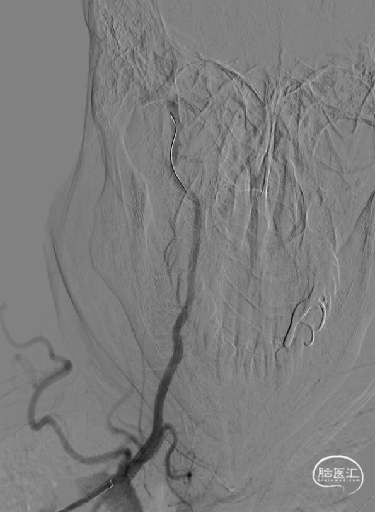

造影示支架完全覆盖狭窄段,与血管壁贴合良好。复查脑血管造影颅内远端血流通畅。

术后影像